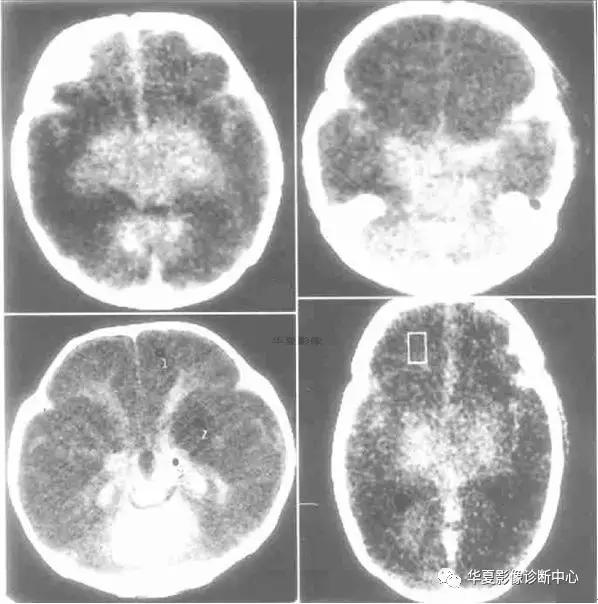

儿童弥漫性脑白质和灰质的密度减低、伴有灰白质界限不清或消失,或灰白质密度反转,而丘脑、脑干和小脑密度相对增高根据“反转征”出现时间分急性和慢性2期。急性指当时CT扫描即有“反转征”,慢性为弥漫性脑萎缩/脑软化伴“反转征”。急性期神经病理学改变主要为大脑皮质和白质发生急性神经元坏死和脑水肿,脑干及丘脑淤点状出血。Baenziter等认为缺氧缺血后大脑皮层第Ⅲ、Ⅳ层神经细胞最易受损,缺血后12小时以上大脑皮层神经细胞即发生嗜酸样变性,基质发生凝固性坏死,2~3 天轴索开始变性,7天左右出现成胶质细胞、脂肪颗粒和新生血管,2~4周形成空洞和软化,进一步论述了缺氧缺血后皮层神经细胞的病理过程。基底节和丘脑损害所发生的密度增高目前有几种认识:国内学者认为系缺氧后上述区域发生大理石样变性所致,表现为神经元的丧失、星形细胞胶样变性及髓鞘过度形成,尤其壳核背外侧与丘脑腹外侧髓鞘化最活跃,需氧量最高,代谢旺盛,对缺氧缺血敏感,因此受累也最为严重。有的则认为是严重缺血后1~2周新生毛细血管网的大量增加或与大脑的白质深部髓质静脉扩张淤血有关,甚至有人认为不是密度增高,而是正常脑组织密度。这种密度增高是相对的,虽然在急性期脑中央区域的密度增高个体间存在一定的密度差异,但本组从未见有像脑血管破裂出血那样的高密度,CT值多在22 HU左右,因此这种密度增高是相对的。

“反转征”的分期,急性期应以生后当时CT扫描结果为准。一般来说,生后3天多以脑水肿为主,其后为脑实质缺氧缺血性损害,所以生后5~10 天扫描较为可靠。慢性期以生后3~8周为妥,此期已出现明显脑软化、脑萎缩,脑实质密度明显低于急性期。急性“反转征”的患儿需要呼吸支持和重症监护,延误治疗者可转变为慢性“反转征”,其密度变化更具有特征性。有人认为重症病人在3个月时即可发生脑软化和脑萎缩,发生率约占HIE病例的20%。与此同时,丘脑与脑干的密度增高较急性期更加显著,如同“增强”一样,CT值22~26 HU,丘脑形态轮廓勾画清楚,犹如雪山的“山丘”,出现这种明显反差的影像学表现可能与脑软化的低密度衬托有关,若不仔细的观察和测量CT值易误为脑出血。

“反转征”主要发生在重度HIE病例中,因此“反转征”可视为重度HIE少见而重要的征象,可把它作为HIE诊断及分级和评价预后的重要依据。

CT“反转征”是新生儿重度缺氧缺血性脑损伤的一种重要CT征象,但并非特异性,也可以在某些疾病中如外伤(虐待伤)、病毒性脑炎等出现。特别应注意慢性“反转征”与HIE的并发症鉴别。众所周知,HIE常见并发症为外部性脑积水和局限性脑软化灶和脑萎缩,前者不存在鉴别问题,后者CT上脑软化灶多发生在顶枕叶或双侧脑室旁白质内,多为局限性,而慢性“反转征”则表现为半球弥漫性低密度区,同时基底节及丘脑等脑中央区域密度增高明显,表现特殊,这点对鉴别诊断有相当重要的价值。因此,重度窒息儿大脑灰白质密度弥漫性减低伴灰白质界限消失或密度反转以及基底节、丘脑、脑干和小脑密度相对增高是重度HIE的特征性CT表现,是诊断急、慢性CT“反转征”的重要依据。急性期脑室受压变窄和慢性期脑室扩大主要与脑水肿和脑软化/脑萎缩有关。“反转征”一旦出现,高度提示脑组织有不可逆性脑损伤存在,预后大多不良,即使存活也将发生脑瘫或智力障碍等后遗症。